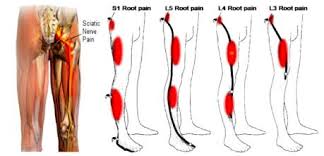

Download Sciatic nerve pain pictures